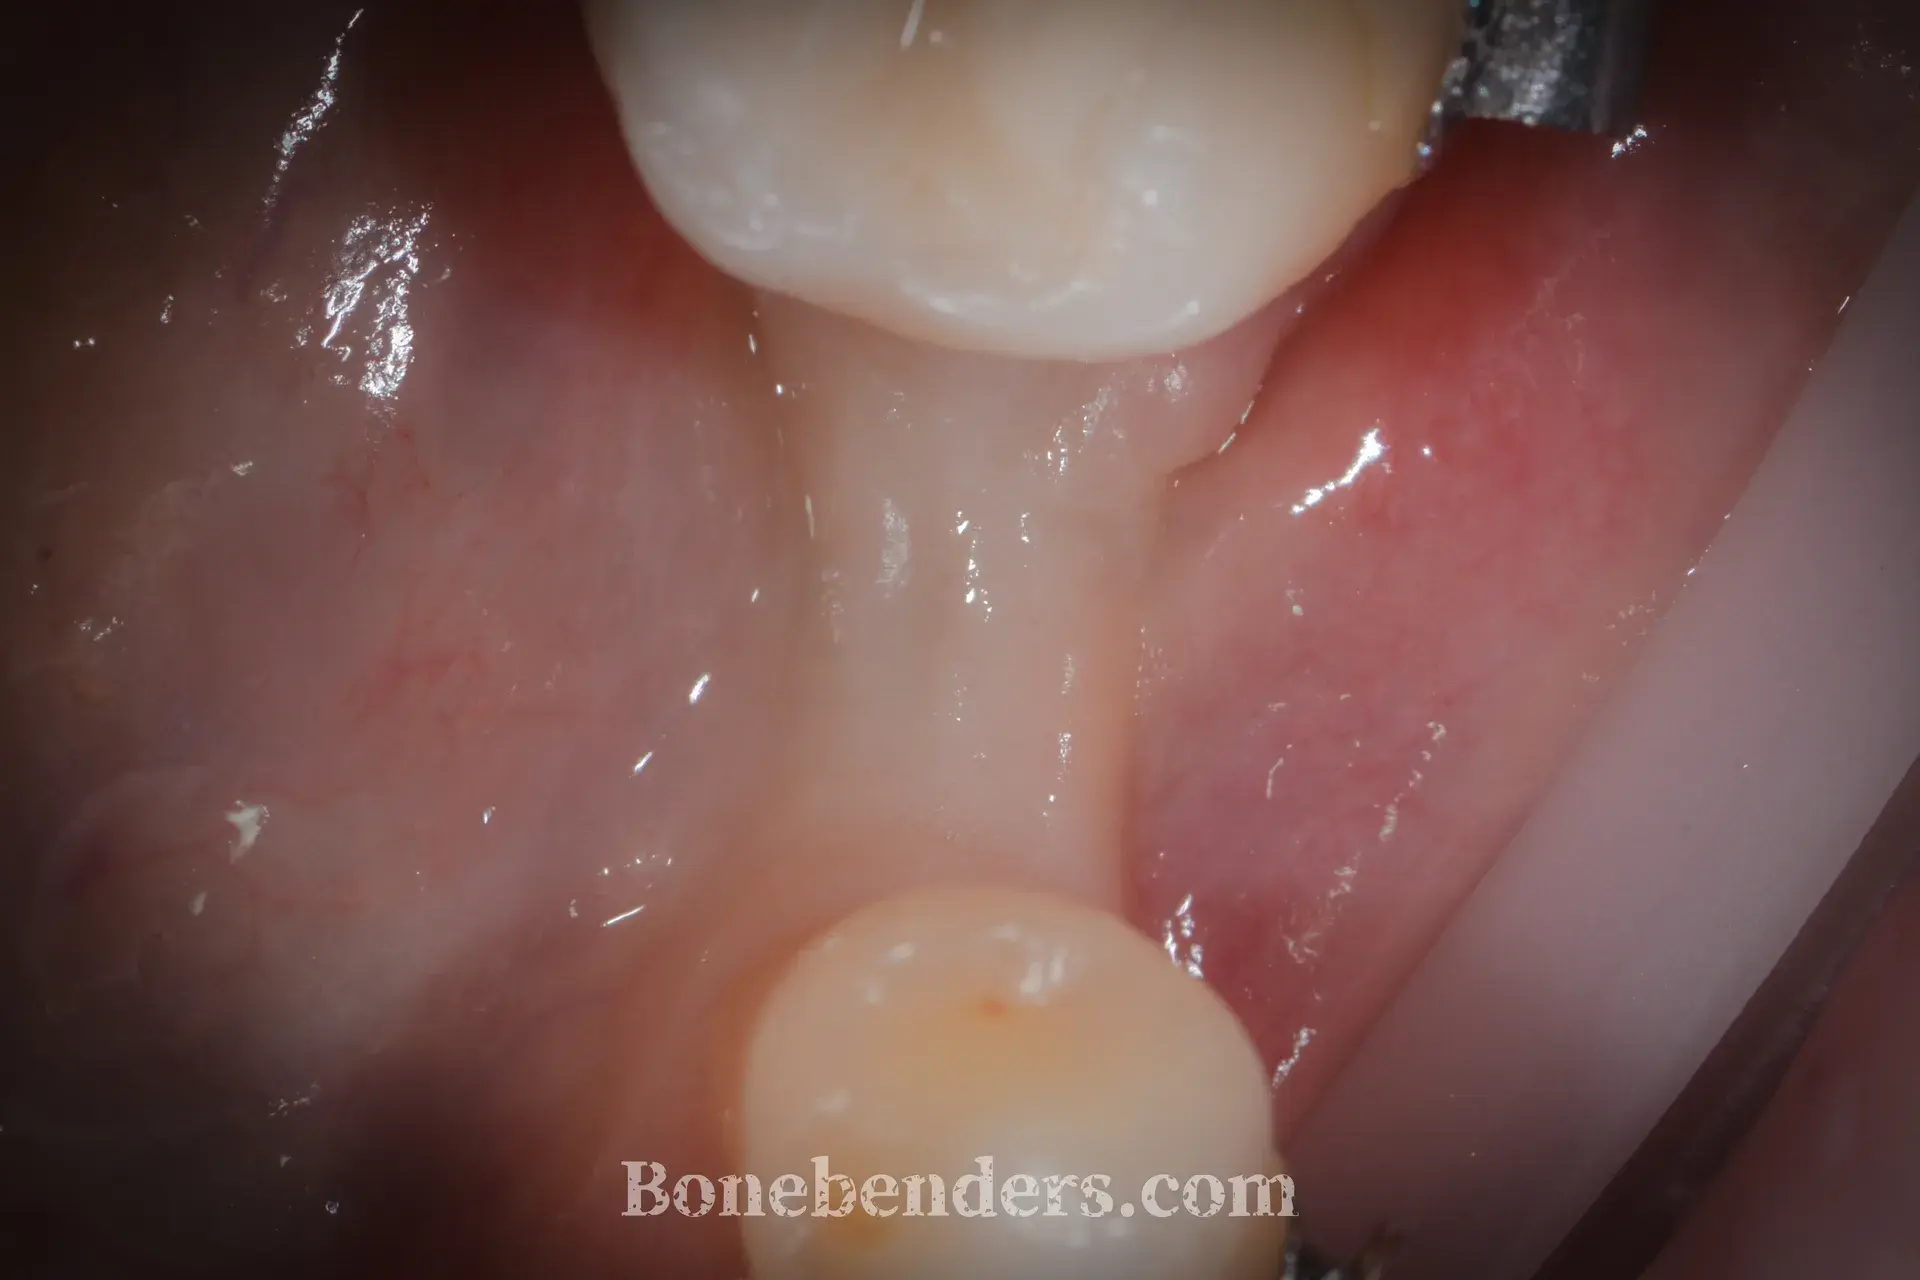

9 casi documentati con fotografie cliniche prima e dopo il trattamento. Ogni caso include la descrizione della tecnica, i tempi di guarigione e i riferimenti scientifici.